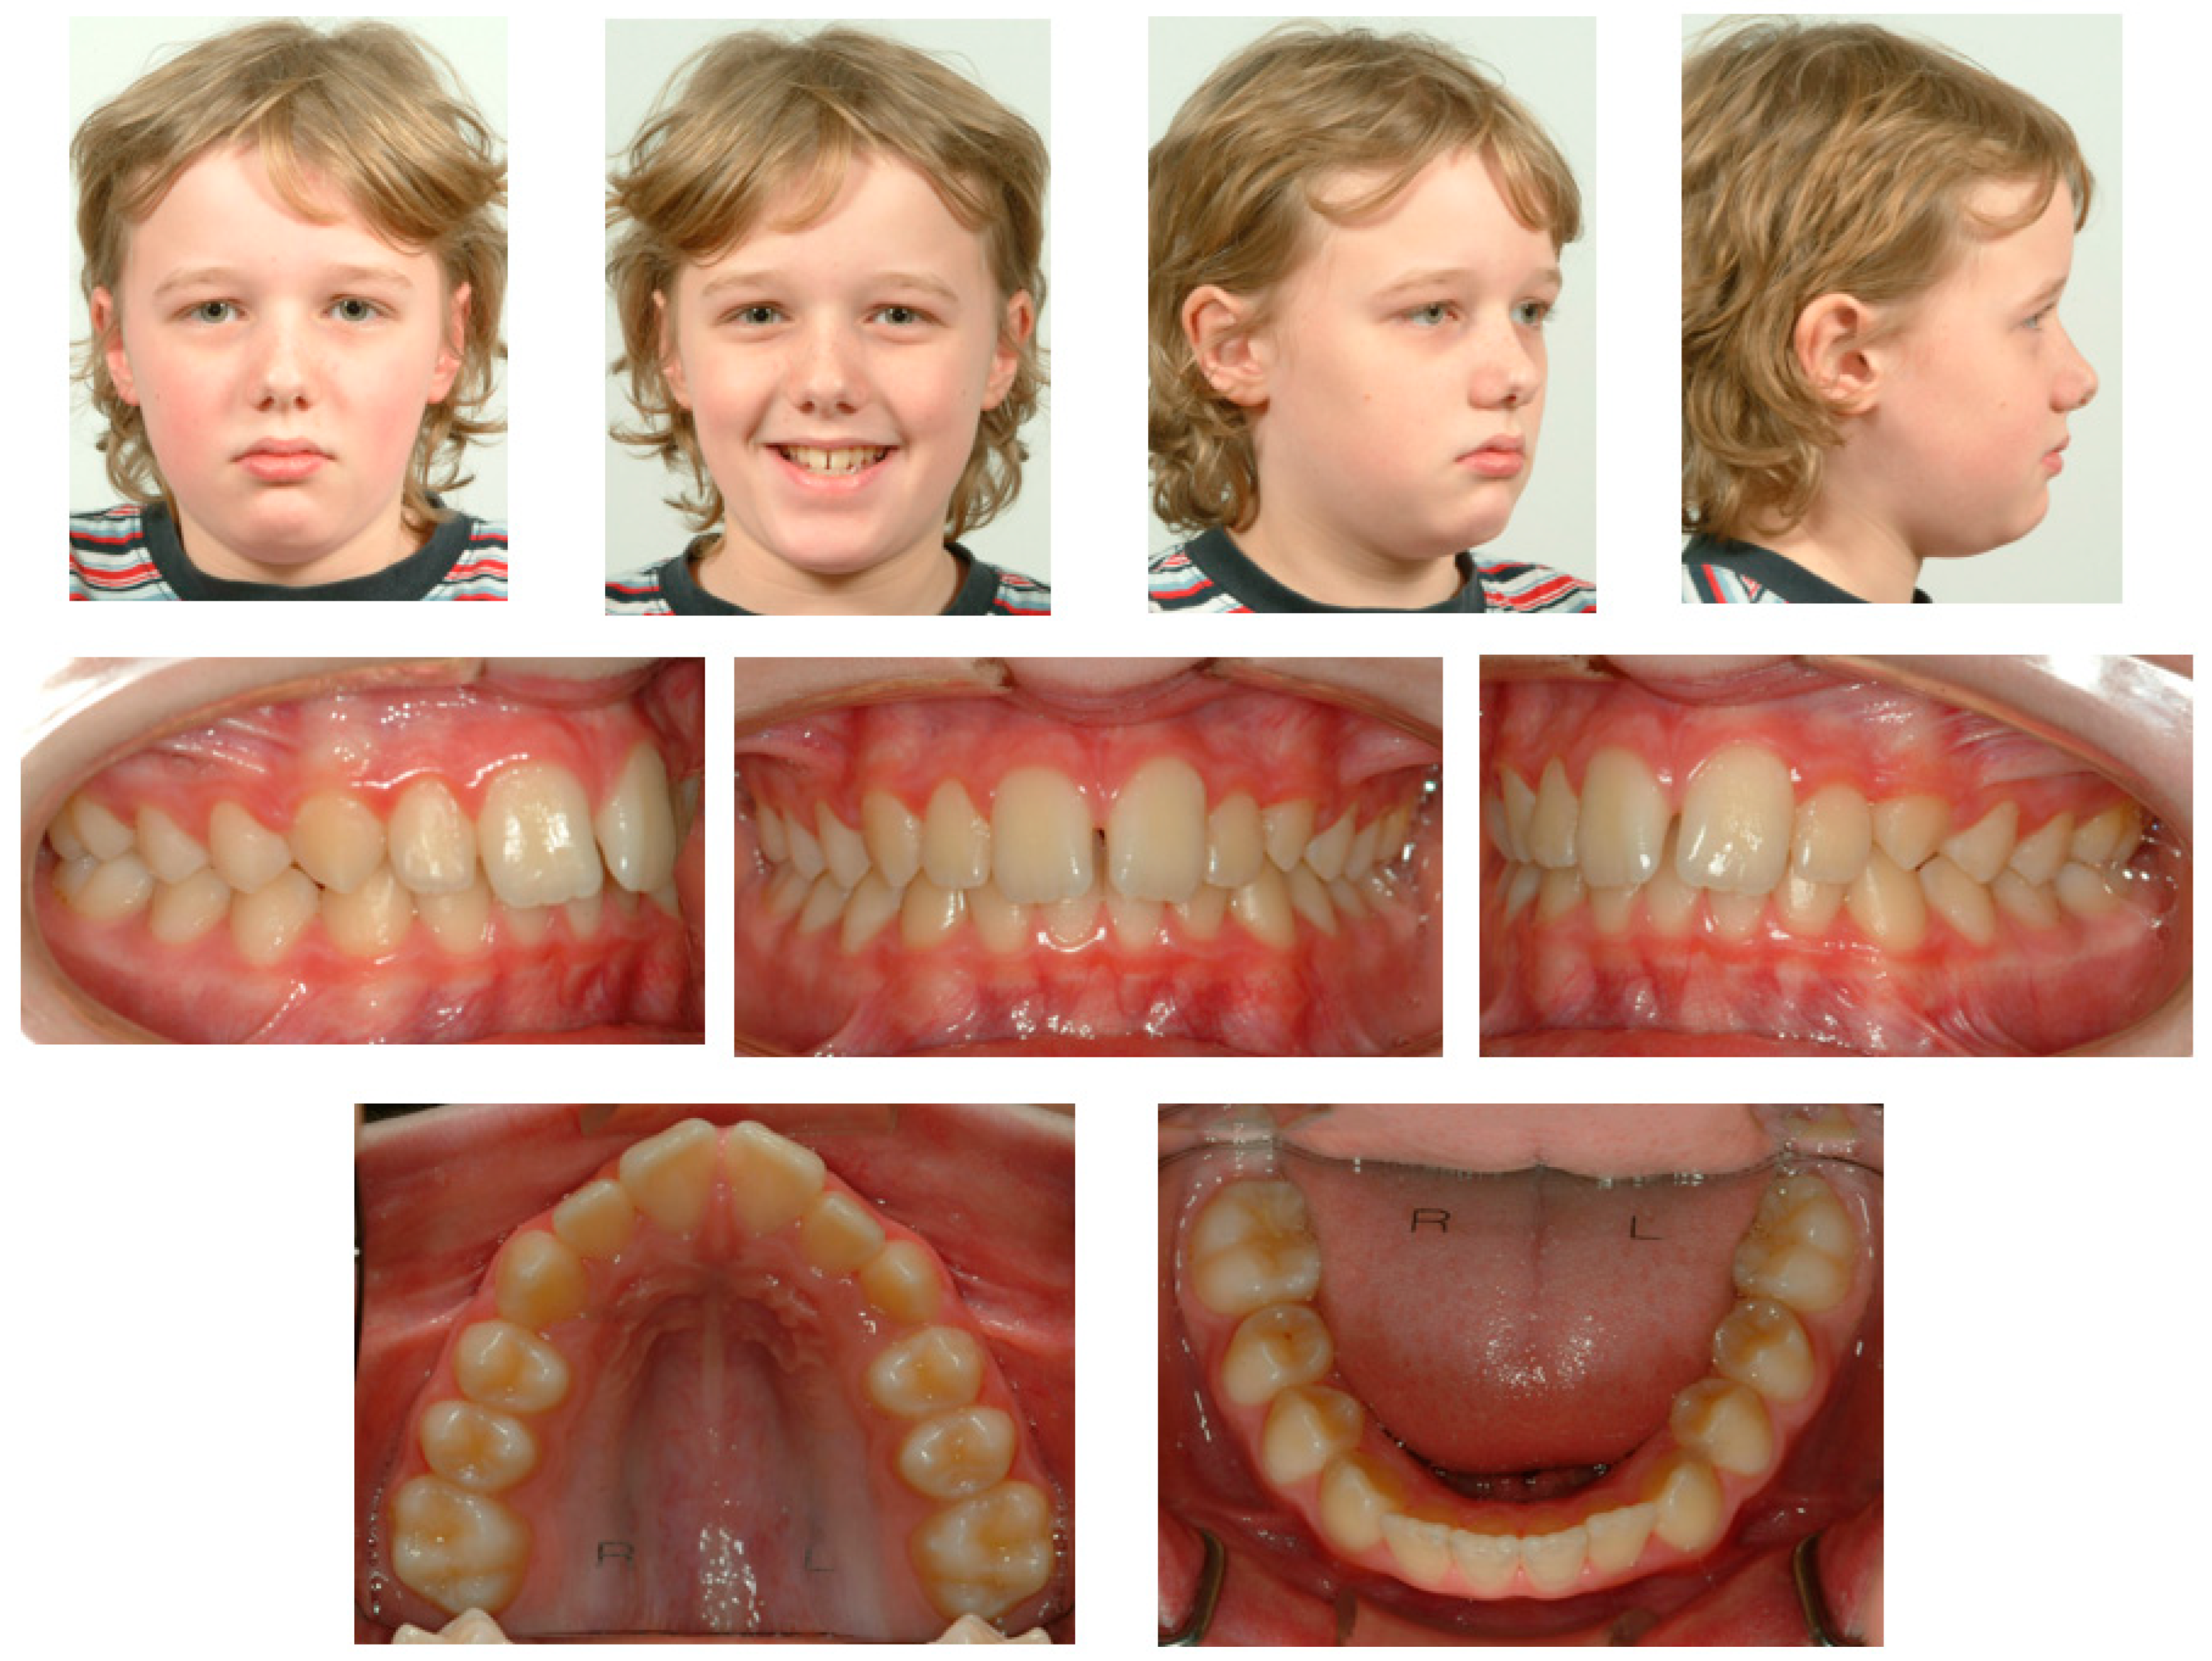

A 21-year-old Caucasian male presented with aesthetic complaints regarding his upper front teeth. He previously underwent orthodontic treatment for a deep bite at the age of 9 years and 11 months for 2 years and 11 months. He was treated with high-pull headgear (Headgear, Dentsply GAC International, NY, USA) followed by full fixed appliances (3M Victory Series APC conventional twin brackets, 3M Health Care Division, London, Canada), and flexible spiral wires (0.0195-inch, 3-strand, heat-treated twist wire, Wildcat, GAC International, Bohemia, NY, USA) were bonded to all the anterior teeth between 13–23 and 33–43 to stabilize the end result (Figure 2). Over the last few years (the moment of onset was unknown), he noted a continuing shift in the position of his upper front teeth (Figure 3A). Aside from his aesthetic complaints, he was concerned that the situation would deteriorate. With regard to his medical history, he only used antihistamines for hay fever if necessary. There was no record of dental trauma, and he was unfamiliar with oral parafunctions. The failure of the fixed retainers had never occurred, and he did not experience any pain or functional constraints.

Figure 3A shows the case at the first presentation. The photographs demonstrate that the 13 shows excessive palatal root torque, and the 23 shows excessive buccal root torque. A cant of the upper incisors can be observed. Moreover, cross-bites are present between the 14 and the 44 and between the 23 and the 34.

The patient presented with a Class I profile and a chin point deviation to the right side (Figure 3A). The intra-oral assessment showed good oral hygiene, a thin gingival biotype, group function on the left and right side, and fixed retainers (0.0195-inch, 3-strand, heat-treated twist wire, Wildcat, GAC International, Bohemia, NY, USA) in the upper anterior segment and lower anterior segment (Figure 3A). The dental cast assessment showed a Class I molar and canine occlusion, an overjet of 2 mm, and an overbite of 3 mm. A cant of the upper incisors was present with palatal root torque of the 13 and buccal root torque of the 23. Crossbites were present between the 14/44 and the 23/34. The arch length discrepancy measurement resulted in values of 0 mm in the case of the maxillary arch and −4 mm in the case of the mandibular arch. No tooth size discrepancy was present. The PAR index resulted in a score of 12 points [22] (Figure 3B). The lateral cephalometric radiograph showed a Class I intermaxillary relationship with an ANB angle of 3.2° (VistaPano S Ceph, Dürr Dental imaging software, Dürr Dental SE, Bietigheim-Bissingen, Germany) (Figure 3C). The panoramic radiograph (VistaPano S Ceph, Dürr Dental imaging software, Dürr Dental SE, Bietigheim-Bissingen, Germany) showed a maxillary sinus mucosal cyst (MSMC) on the right side and external apical root resorption located at the 12, 11, and 21 (Figure 3D).

Figure 3. Documentation before orthodontic re-treatment. (A) Extra-oral and intra-oral photographs. (B) Dental casts. (C) Lateral cephalometric radiograph. (D) Panoramic radiograph.